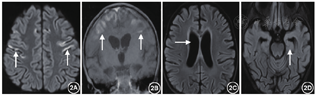

辅助检查(括号内为正常参考):血乳酸多次增高,波动在5.2~14.9 mmol/L(参考值0.5~2.2 mmol/L,以下同);血气分析示:酸碱度(pH)下降明显,波动在7.09~7.30(7.35~7.45)之间,碱剩余(BE)增高明显,波动在-21.5~-5 mmol/L(-4~2 mmol/L);碳酸氢根(HCO3-)16~20 mmol/L(22~27 mmol/L)提示呼吸性酸中毒合并代谢性酸中毒改变。肝酶+心肌酶+电解质提示:谷丙转氨酶(ALT)71.80 IU(0~40 IU),谷草转氨酶(ALT)98.40 IU(0~40 IU);肌酸激酶(CK)587.7 IU(40~190 IU),肌酸激酶同工酶(CK-MB)63.10 IU(0~50 IU),乳酸脱氢酶475 IU(0~450 IU),血清钾3.18 mmol/L(3.5~5.5 mmol/l),血钠139.30 mmol/L(135~145 mmol/L),其余正常。甲状腺功能八项:三碘甲状原氨酸(TT3)0.791 nmol/L(1.4~3.4 nmol/L),促甲状腺激素(TSH) 2.94 IU/ml(0.34~4.6 IU/ml);甲状腺素(TT4)42.05 nmol/L(76.6~189 nmol/L)偏低;游离T3(FT3)42.05 nmol/L(3.68~8.46 nmol/L),提示甲状腺功能低下,其余均正常。血氨、同型半胱氨酸及铜蓝蛋白正常;脑脊液常规、生化、乳酸、病原学检查、自身免疫性脑炎相关抗体检查:均未见异常;血尿串联质谱分析:未见异常。视频脑电图(VEEG):背景活动节律慢化,额、中央、颞区(右侧著)为主棘波稍多量发放。神经电图+肌电图:双上下肢体感通路检查潜伏期延长,波幅偏低。头颅MRI(病程第9天)提示双侧丘脑、大脑脚、脑干对称性片状稍长T2信号影(图1)。复查头颅MRI(病程第40天)提示:脑损伤,颅内部分异常信号较前显示增多,原有部分异常信号较前显示稍少,双侧脑室稍扩大;双侧大脑半球脑沟裂增宽加深,第三、第四脑室饱满(图2)。脊髓MRI平扫+增强未见明显异常。

硫辛酰基转移酶-1缺乏症患儿头颅影像学显示髓鞘形成延迟、双侧额叶白质异常和小脑萎缩,皮质萎缩,双侧丘脑、脑干、基底节等对称性异常等常见。有报道的5例起病患儿中例1及例5有脑萎缩、发育延迟,侧脑室扩张;丘脑异常信号;例1及例5患儿头颅磁共振波幅(MRS)可见乳酸峰,同时监测血乳酸升高,该现象可能与谷氨酰胺、脯氨酸升高神经毒性作用于线粒体导致能量供应障碍有关[8, 16]。本例起病年龄较晚,头颅影像学提示脑干、丘脑受累显著,未查头颅磁共振波普检测乳酸峰累积状况,结合本例治疗后复查头颅MRI提示多部位有进展,受累较前加重,脑萎缩明显,与硫辛酰基转移酶-1缺乏症经典头颅MRI改变不完全相符,提示生活质量欠佳及预后总体不良,可继续随访观察临床转归及影像学改变。